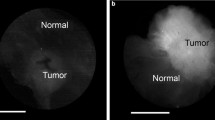

A total of 570 cavity margin surfaces in 40 patients were imaged intraoperatively and compared to excised specimen histopathology to develop the tumor detection algorithm. Image acquisition for each 2.6-cm-diameter margin surface took approximately 1 s. Invasive ductal carcinoma, invasive lobular carcinoma, invasive carcinoma with mixed ductal and lobular features and DCIS all produced similar fluorescent signals, with tumor fluorescent signal 3.78–4.11 times greater than normal tissue signal (Fig. 1). Tumor could be distinguished from normal tissue in ex vivo transected lumpectomy specimens regardless of breast mammographic density or patient menopausal status.

a–b Ex vivo LUM Image of the marginal aspect of a comprehensive shaved cavity margin*; Perpendicularly sectioned multifocal, grade 2 ductal carcinoma in situ (DCIS) with necrosis, calcifications and cancerization of lobules, < 1 mm to inked margin. c–d Ex vivo LUM Image of lumpectomy cross section*; grade 1 invasive ductal carcinoma (IDC), 0.9 cm across. e–f Ex vivo LUM Image of lumpectomy cross section*; grade 3 IDC with extensive intraductal component and prominent lymphocytic infiltrate, 1.3 cm across. g–h In vivo LUM Image of final margin with red highlighting for signal above threshold; grade 1 to 2 invasive lobular carcinoma, extensive lobular carcinoma in situ, focal atypical ductal hyperplasia, fibrocystic changes with usual ductal hyperplasia and apocrine cysts, 0.6 cm present at the inked margin along a broad front. i–j Ex vivo LUM Image of the marginal aspect of a comprehensive shaved cavity margin*; Perpendicularly sectioned grade 2 to 3 DCIS with associated necrosis and calcifications spanning up to 0.7 cm, present or < 0.1 cm from new inked margin along a broad front. *The LUM Imaging System algorithm for signal-highlighting produces red highlights during in vivo imaging. Some ex vivo images are displayed as black and white images without red highlights